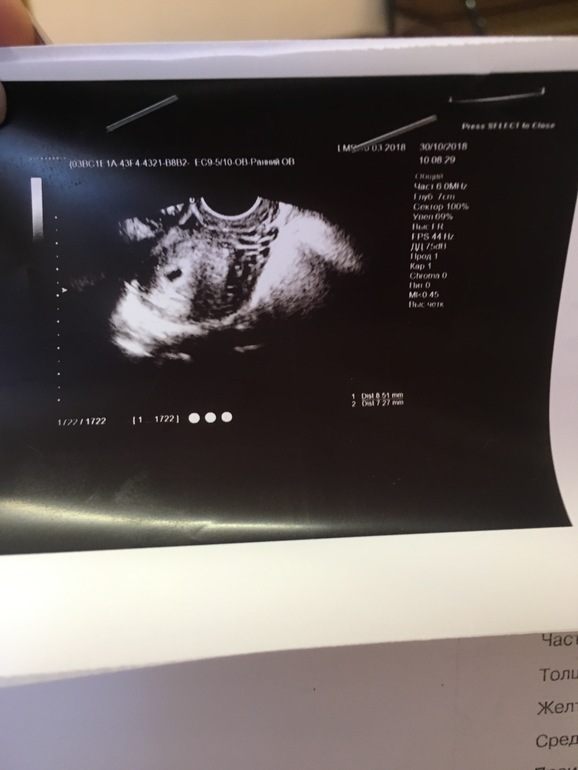

Девочки, как такое может быть? Неделю назад ПЯ было внизу матки, с яичниками было все в порядке, но ставили угрозу. Сегодня ПЯ поднялось, но увеличен левый яичник, предлагают госпитализацию. Такого ведь не бывает!

Смущает Ее ещё то что ХГЧ позавчера 1540, а ПЯ сроку не соответствует

То что нет желточного мешка меня бы больше беспокоило, чем просто увел.яичник. Переделайте в нормальном месте.

Эта врач не наилучшая здесь, если честно. Уже были подобные казусы с ней. При сгустке в матке ставила мне шеечную беременность. Неделю назад поставила угрозу и ПЯ внизу матки, сегодня это. Я в шоке. Но ведь у меня в этом яичнике изначально было желтое тело, лжёт из-за него он увеличен? А и ещё Ее смутило что хгч позавчера был 1540, а ПЯ сроку не соответствует, поэтому ВБ

Это уже не ВБ, если ПЯ в матке. Следить за ростом ХГЧ и через пару дней переделать узи в нормальной клинике.

Хгч хорошо растёт, 28 был 1540, это и смутило врачиху, типа ПЯ не соответствует сроку. Но могло быть позднее зачатие, 6-7 октября только у нас был ПА, перед этим воздерживались. Вот моя заведующая сказала что если так, то все ок, через 10 дней УЗИ если все будет в порядке